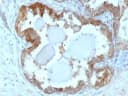

Anti-HSP27(G3.1), Biotin conjugate

Anti-HSP27(G3.1), Biotin conjugate - image 1

Anti-HSP27(G3.1), Biotin conjugate - image 2

Anti-HSP27(G3.1), Biotin conjugate - image 3

Anti-HSP27(G3.1), Biotin conjugate - image 4

Anti-HSP27(G3.1), Biotin conjugate - image 5